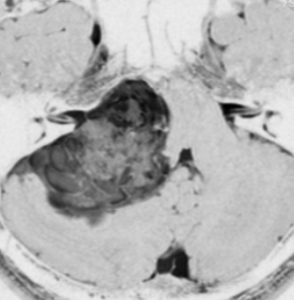

症例:延髄軟膜下 のもの subpial schwannoma in the medulla oblongata

40代男性です。咽せる,頚部痛という迷走神経症状で発症し,小脳失調がでてから腫瘍が発見されました。ある病院で第4脳室と脳槽内ののう胞性部分を摘出され,残存腫瘍摘出の目的で紹介されました。残った腫瘍は迷走神経根の腹側の延髄内部に食い込み,延髄軟膜下 subpial に主体がありました。nearly complete resectionをして経過を見ています。術後は嚥下障害が悪化したのですがかなり回復して,嗄声はなく自宅で食事をする日常生活にもどれました。